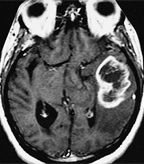

MRI of glioblastoma multiforme